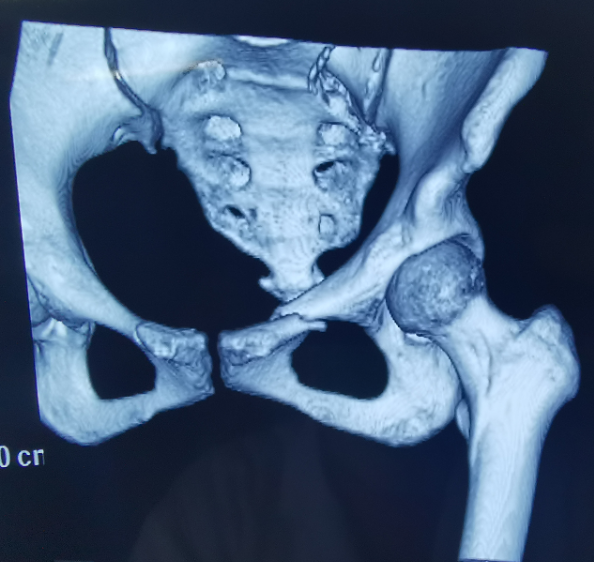

外傷致骨盆骨折

傳統(tǒng)手術(shù)方式切口大

患者為22歲年輕女性,因車禍致骨盆骨折。骨盆骨折是一種復(fù)雜的創(chuàng)傷,傳統(tǒng)手術(shù)方式需要比較大的切口,而且骨盆內(nèi)有大量復(fù)雜血管和神經(jīng),手術(shù)難度和風(fēng)險(xiǎn)極大,是很多骨科醫(yī)生的禁區(qū)。

在傳統(tǒng)骨科手術(shù)中,反復(fù)使用X線透視,有時(shí)須經(jīng)常調(diào)整或更改手術(shù)固定方式,常常需要多年的臨床經(jīng)驗(yàn)積累,也難免意外頻發(fā),畢竟人眼判斷和X線透視單平面觀察的局限性是客觀原因。